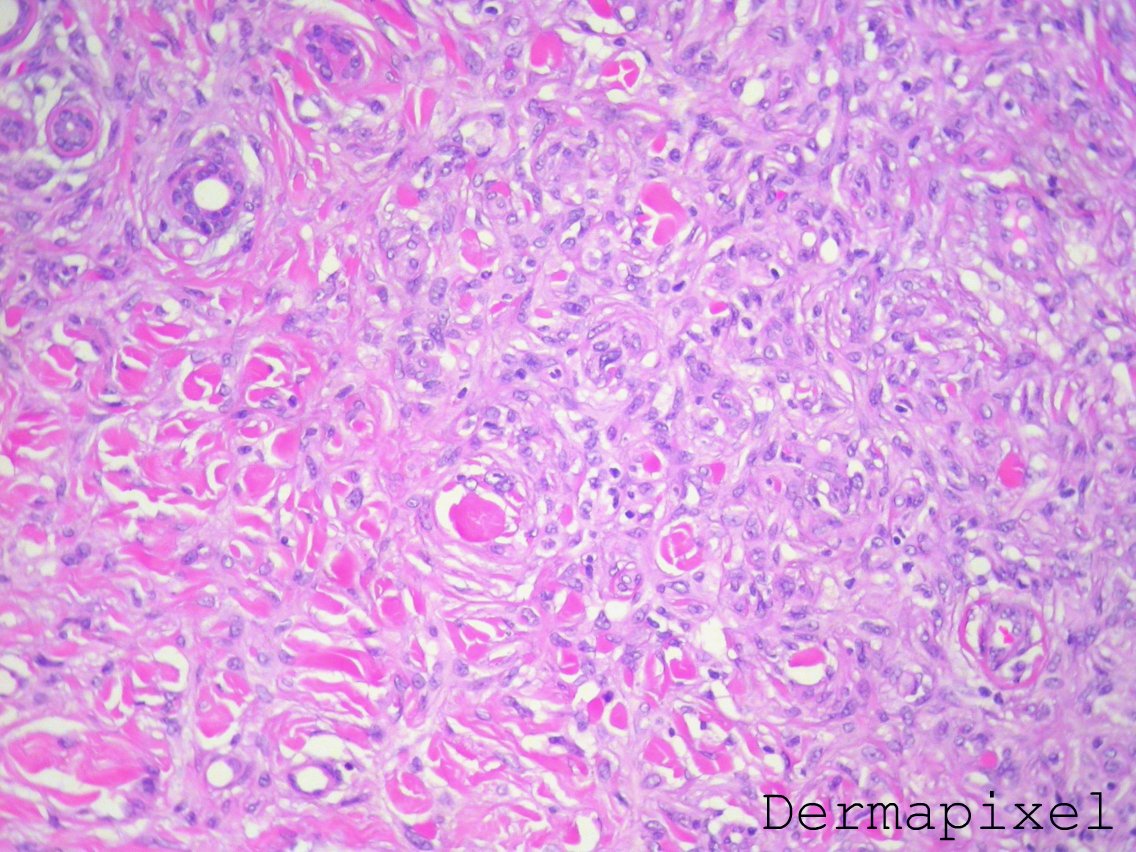

Dermatofibromas are histologically defined by a dermal proliferation composed of spindled fibroblasts and histiocytes arranged in fascicles with intervening entrapped dense hyalinized collagen bundles. Dermatofibromas may also be called benign fibrous histiocytomas.

Dermatofibroma, fibrous histiocytoma, histiocytoma cutis, cutaneous fibrous histiocytoma dermatofibroma. La diagnosi di dermatofibroma spesso può essere fatta clinicamente. Dermatofibroma frequently develops on the extremities. A dermatofibroma (df) is a common, benign tumor composed of fibroblastic and histiocytic cells. Le lesioni vengono talvolta sottoposte a biopsia per escludere una proliferazione melanocitica (p. Dr amanda oakley, dermatologist, hamilton, new zealand, 1997. Df presents clinically with several different reported variants. Dermatofibroma (aka benign fibrous histiocytoma) is one of the most common spindle cell lesions in the skin, but they can sometimes be tricky to recognize. Dermatofibroma (superficial benign fibrous histiocytoma) is a common cutaneous nodule of unknown etiology that occurs more often in women. One rare variant is hemosiderotic df (hdf). Dermatofibroma also known as histiocytomas are noncancerous skin growths which are quite common. Dermatofibromas may also be called benign fibrous histiocytomas.